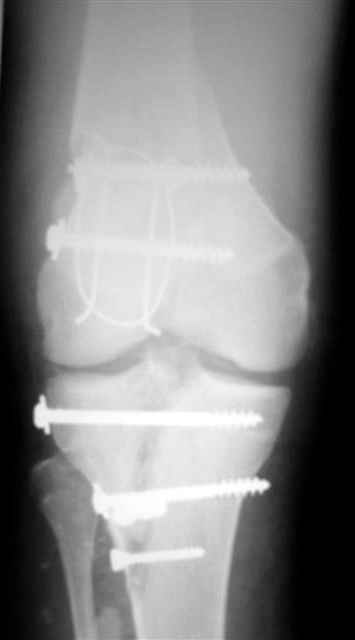

Re: открытый перелом мыщелков бедра, латерального

Вид раны на сегодня...

4 cутки после травмы.

Спасибо за комментарии. Травма тяжелая с проблематичным прогнозом для функции коленного сустава( изначально травма разгибательного аппарата с последующим частичным некрозом собственной связки надколенника и о обнажением рефиксированного фрагмента бугристости большеберцовой кости, дефектом центрального отдела суставной поверхности большеберцовой кости и медиального отдела капсулы сустава).